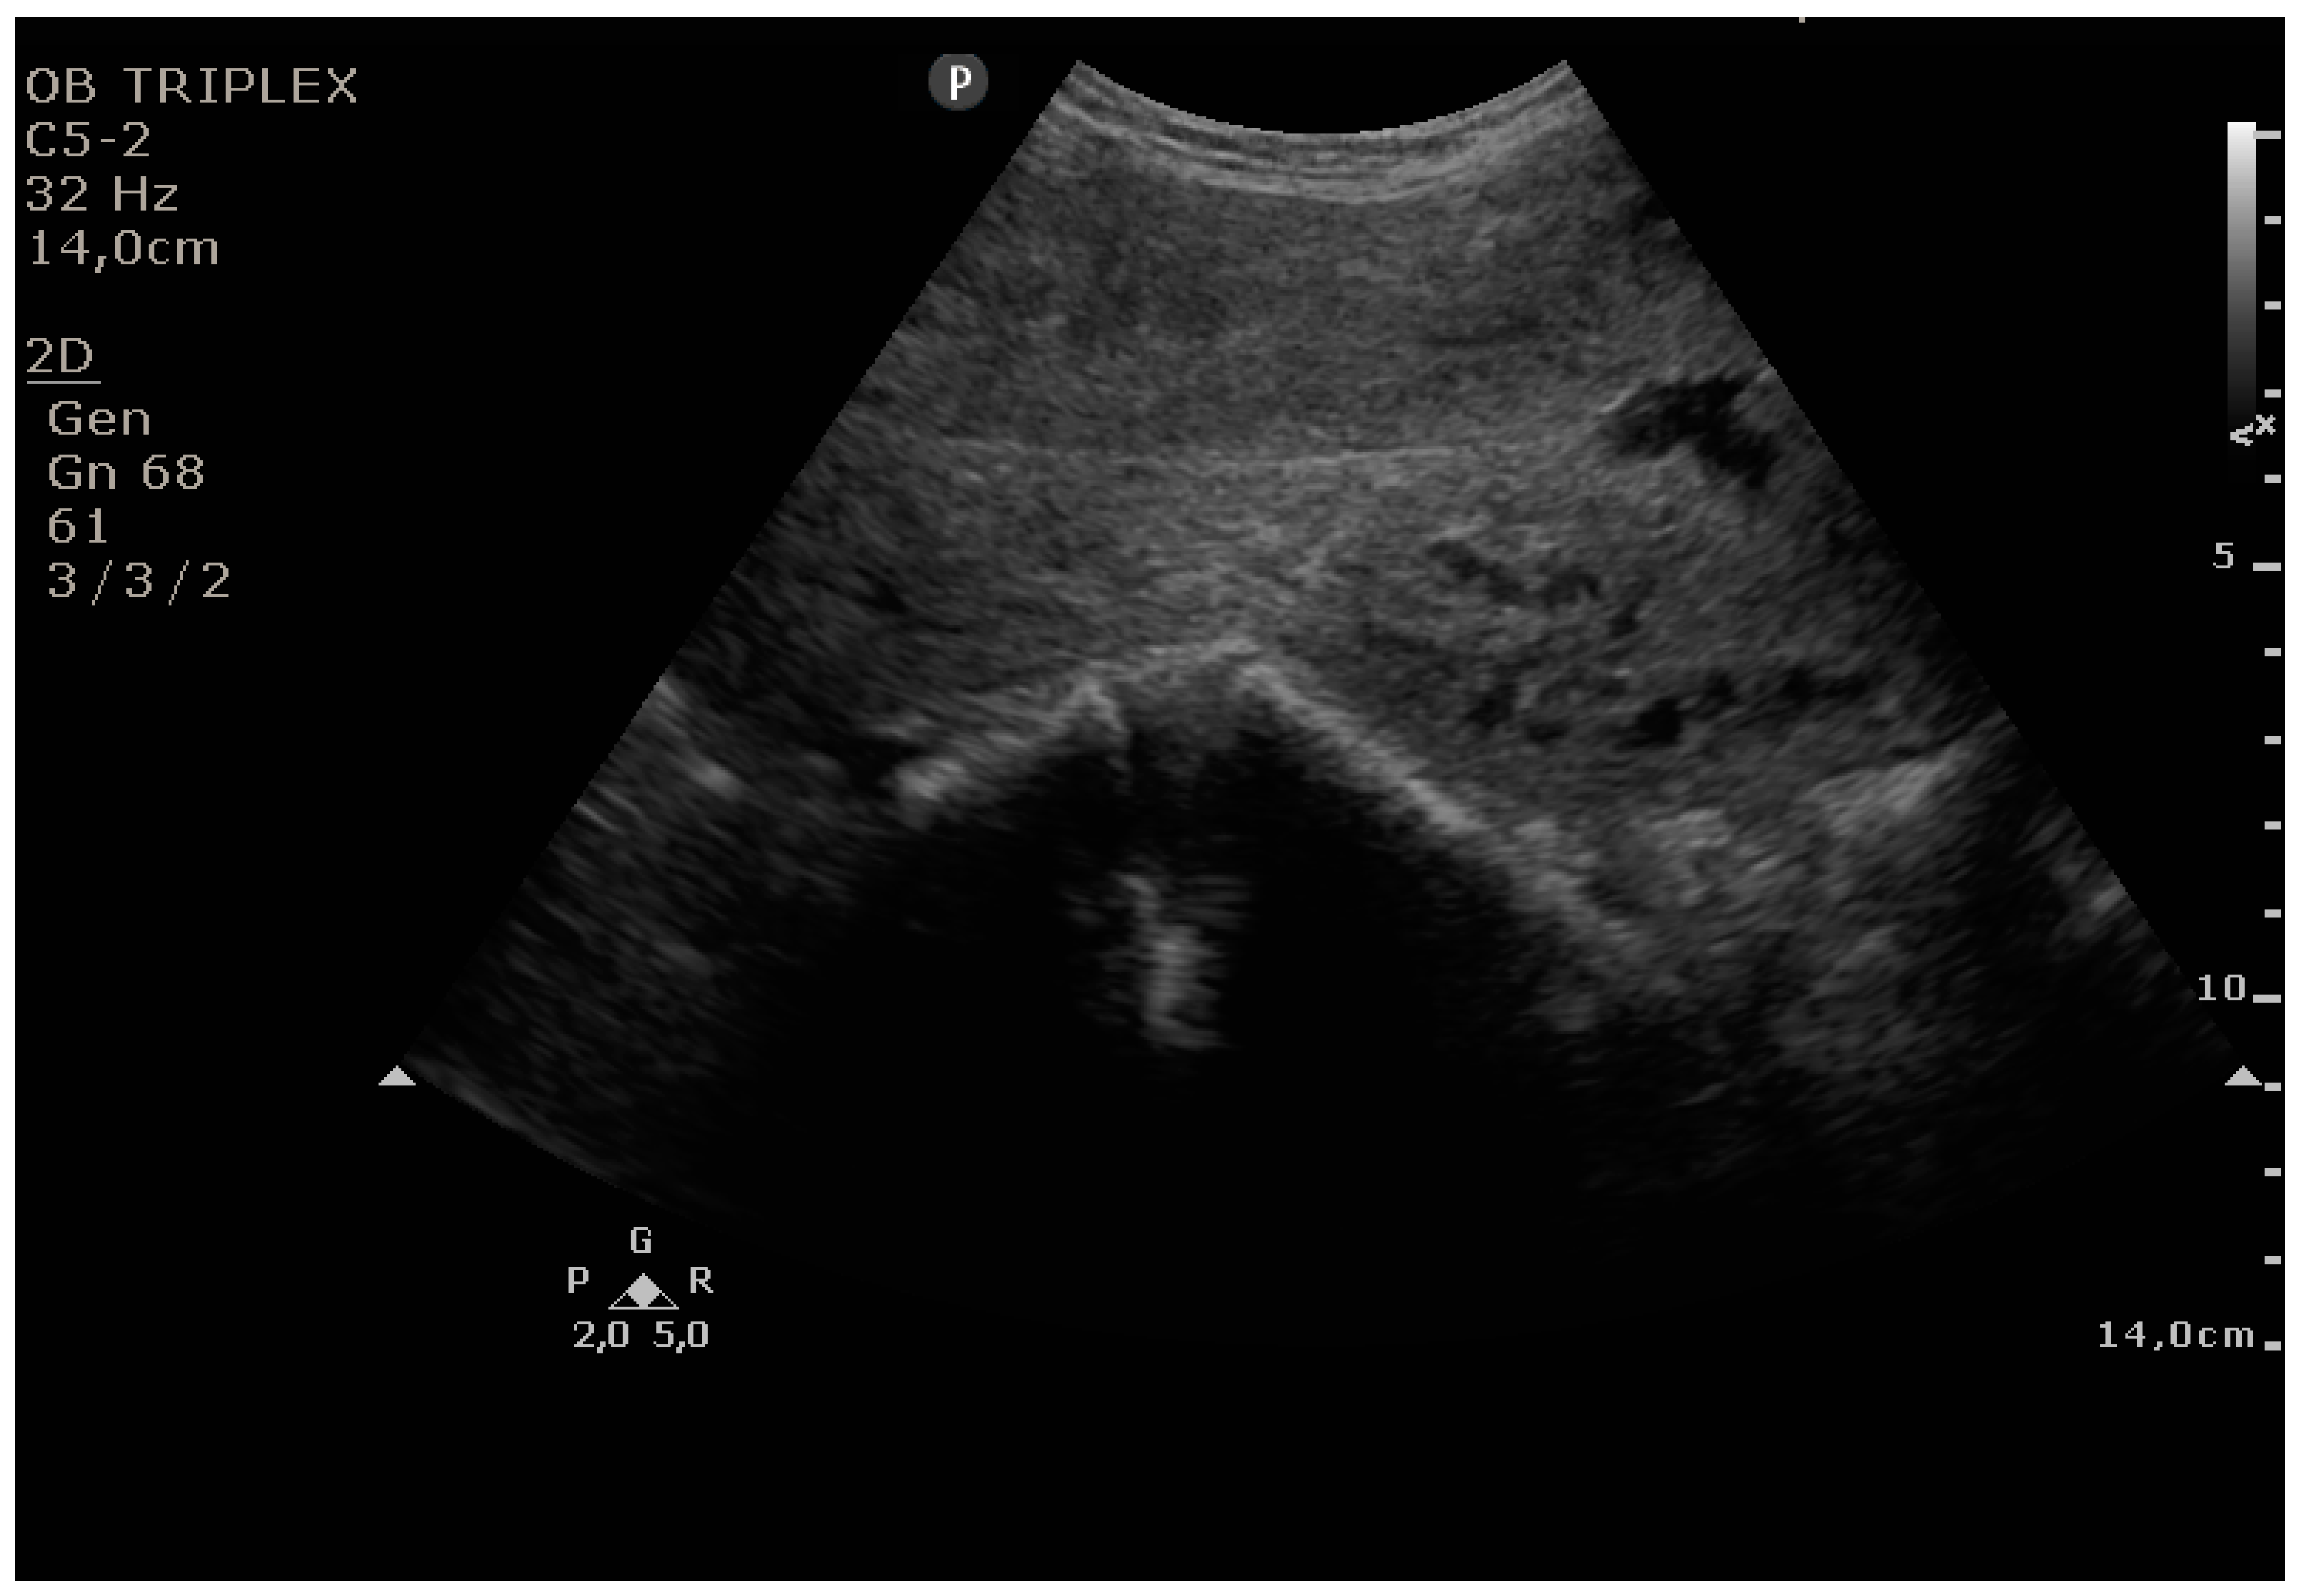

The PUUS method evaluates the proportion of the endometrial length occupied by blood or debris, as follows (Figure 1, Figure 2, Figure 3, Figure 4 and Figure 5):

Figure 2.

Grade 1: less than one-quarter of the endometrial length occupied by blood or debris.